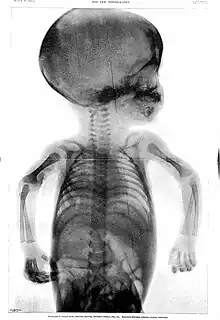

Esse caráter temporário se deve ao fato de que sua função é promover o crescimento dos ossos longos do membro. Trata-se da lâmina epifiasial, um disco cartilaginoso encontrado entre a diáfise e cada uma das duas epífises em ossos longos do indivíduo em fase de crescimento. Ela permite o aumento do comprimento do osso a partir da proliferação desse tecido cartilaginoso, seguida de sua substituição por tecido ósseo. Quando a cartilagem é totalmente ossificada, o aumento de comprimento do osso cessa. As ossificações mais tardias costumam se completar aos 20 anos de idade.[3][20]

Em bebês, nem mesmo as epífises são visualizadas inicialmente, pois têm ossificação mais tardia. Assim, em suas radiografias da mão, os espaços aparentemente vazios são ainda maiores. Só depois que as epífises se ossificam, a porção restante de cartilagem hialina (lâmina epifisial) é observada, entre cada epífise e a diáfise.[21]

Radiografia de mãos adulta e infantil. O bebê nem tem epífises ossificadas, enquanto o adulto até fechou suas lâminas epifisiais.